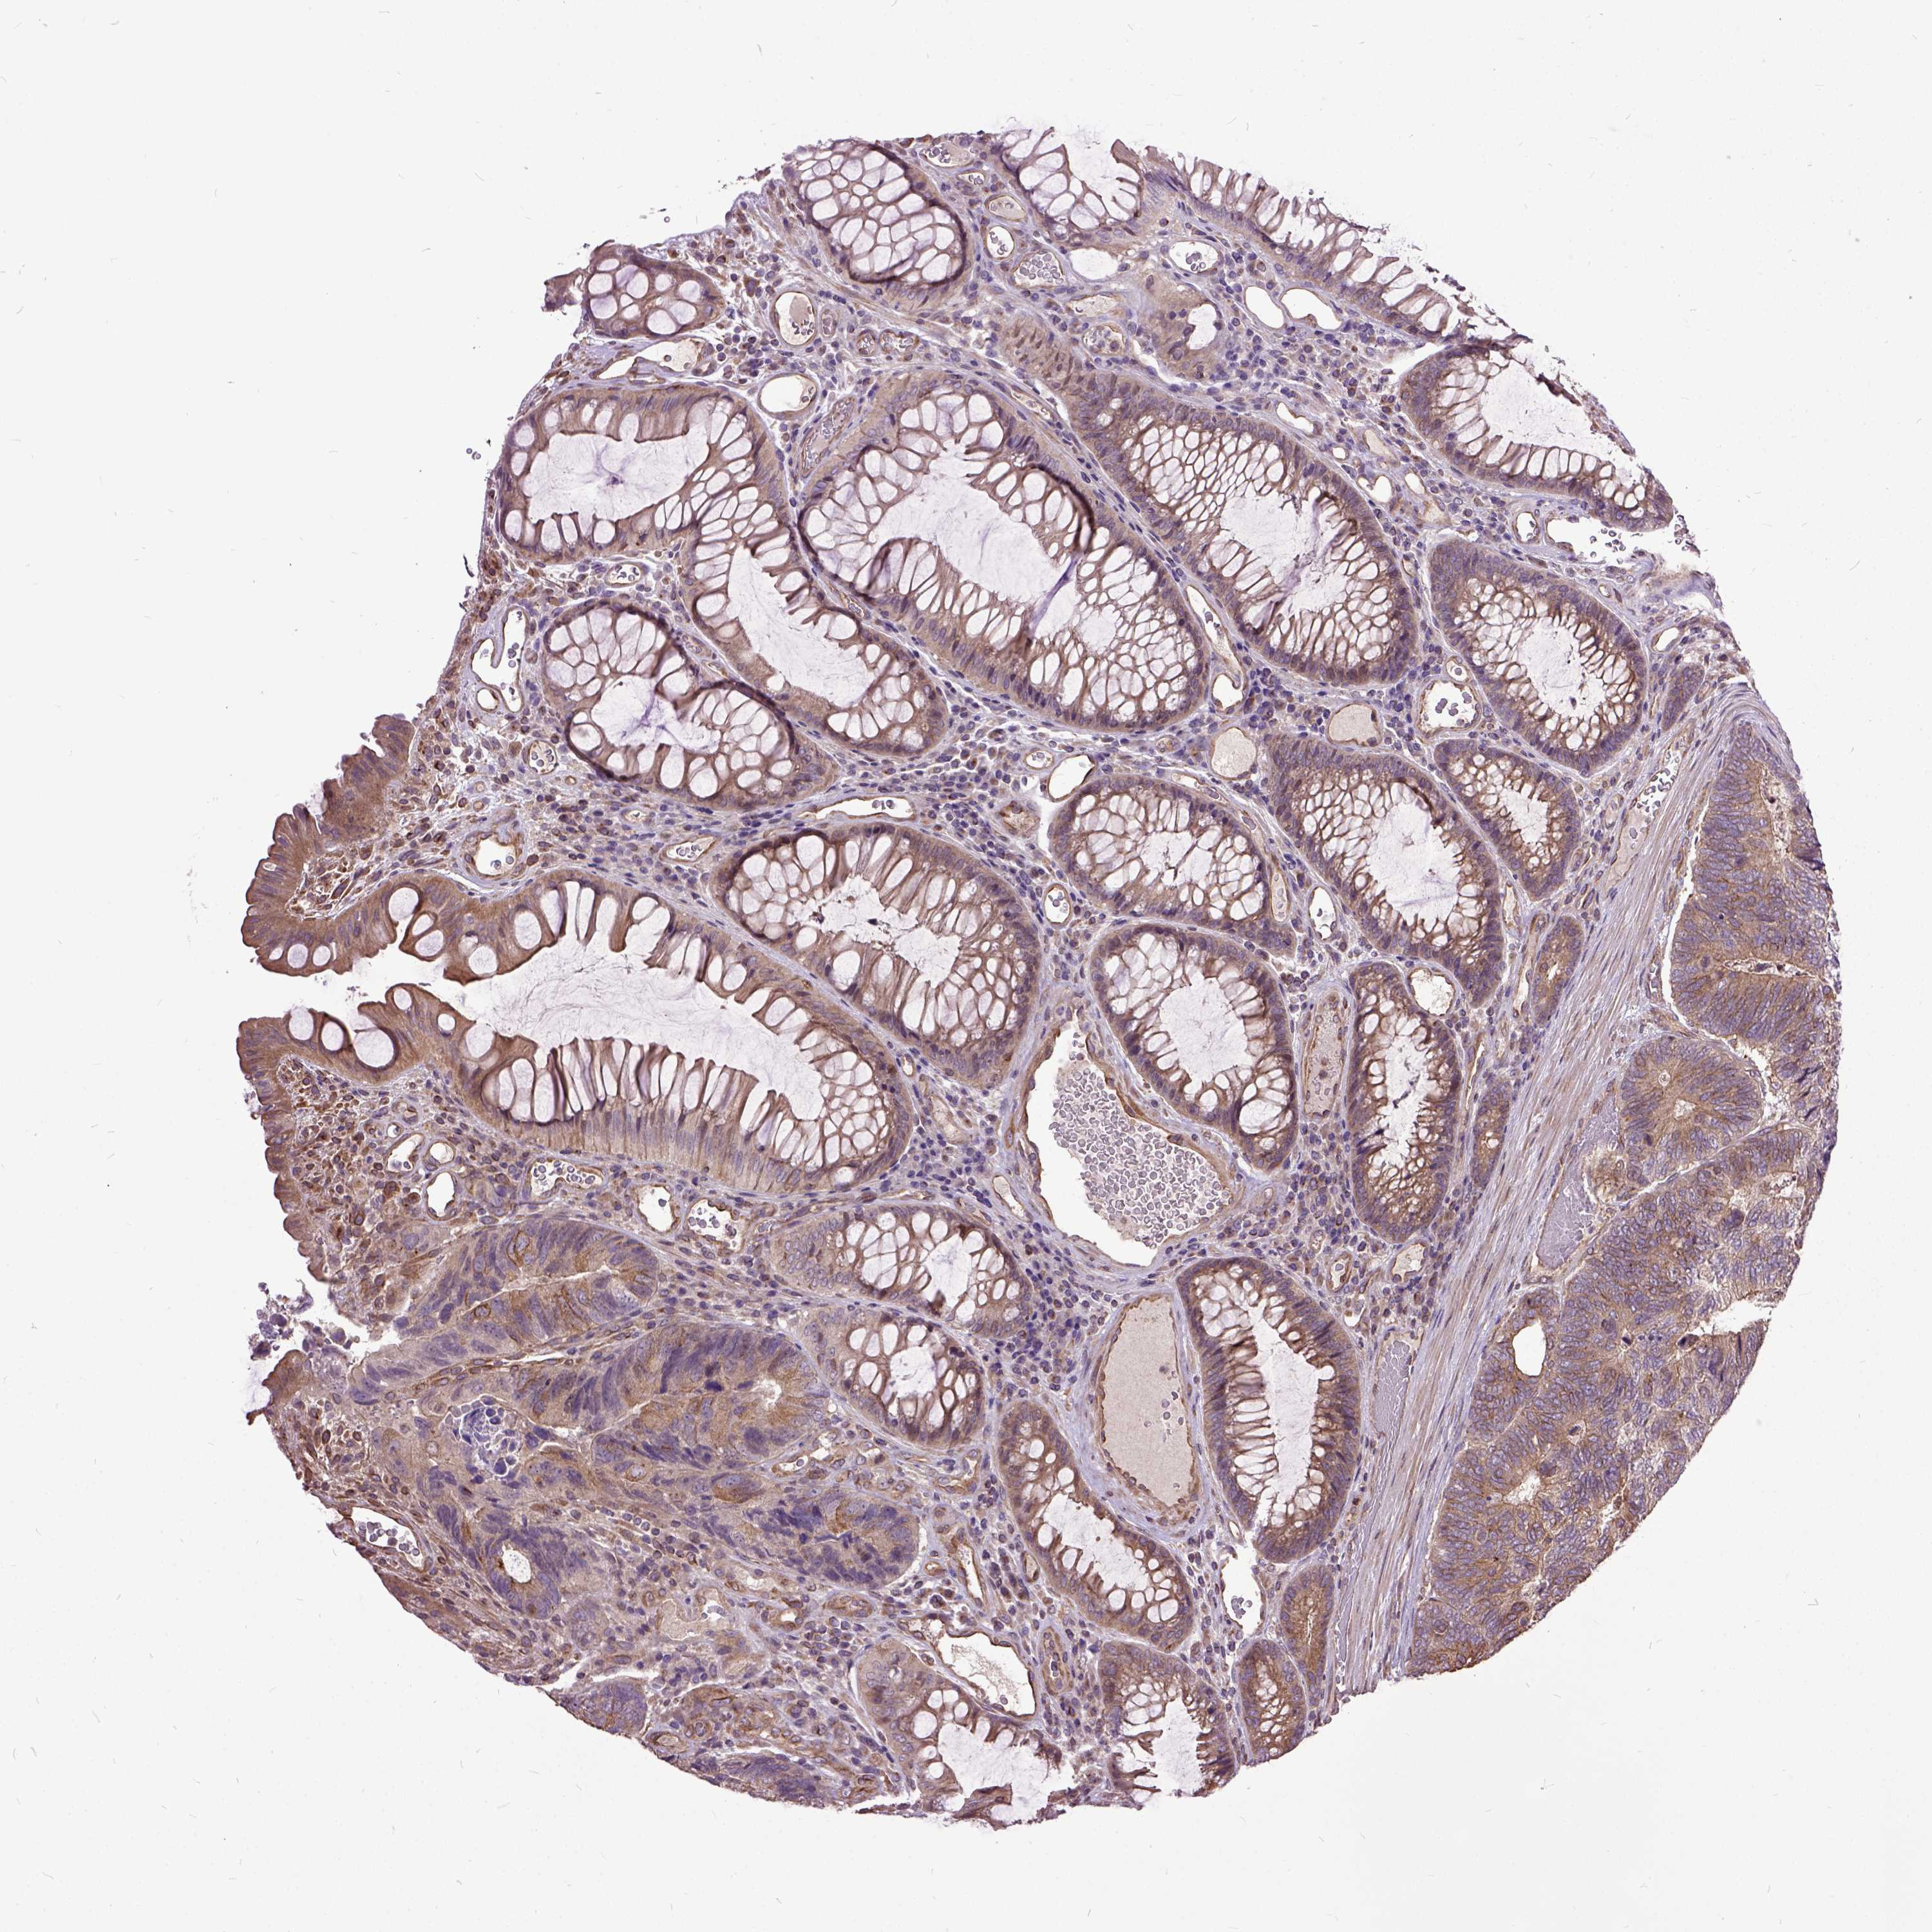

Colorectal cancer

Human cancer

Colon adenocarcinoma

Rectum adenocarcinoma